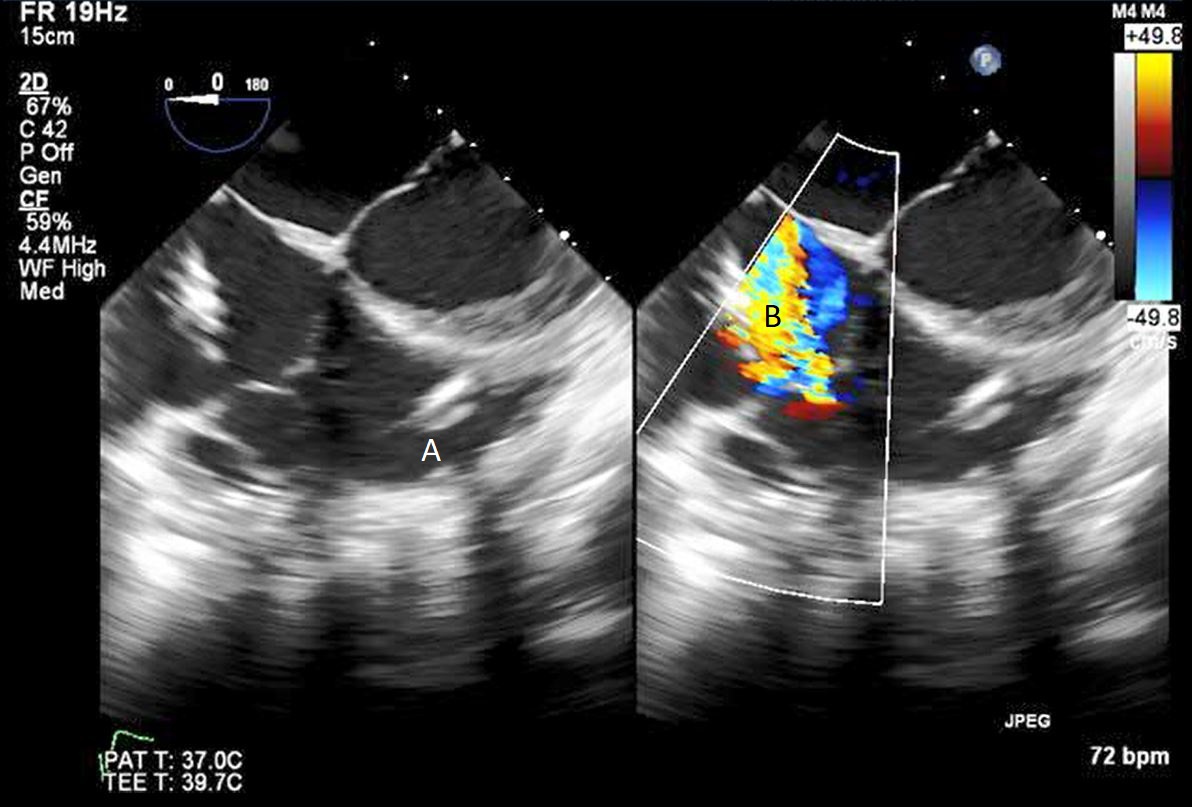

When examining the inflow cannula of the LVAD, the inflow cannula should be orientated and aligned with the mitral valve [47] (Figs. 19,20). Laminar flow from the ventricle to the device suggests a correctly aligned inflow cannula [56]. Obstruction of the inflow cannula manifests with increased turbulence and elevated doppler velocities [47].

Fig. 19.Transthoracic echocardiogram PLAX image demonstrating inflow cannula at LV apex (A) and AV systolic closure (B).

Fig. 20.Transesophageal echocardiogram four chamber image with the LVAD inflow cannula pointing towards the septum (A). (B) LV (C) LA.